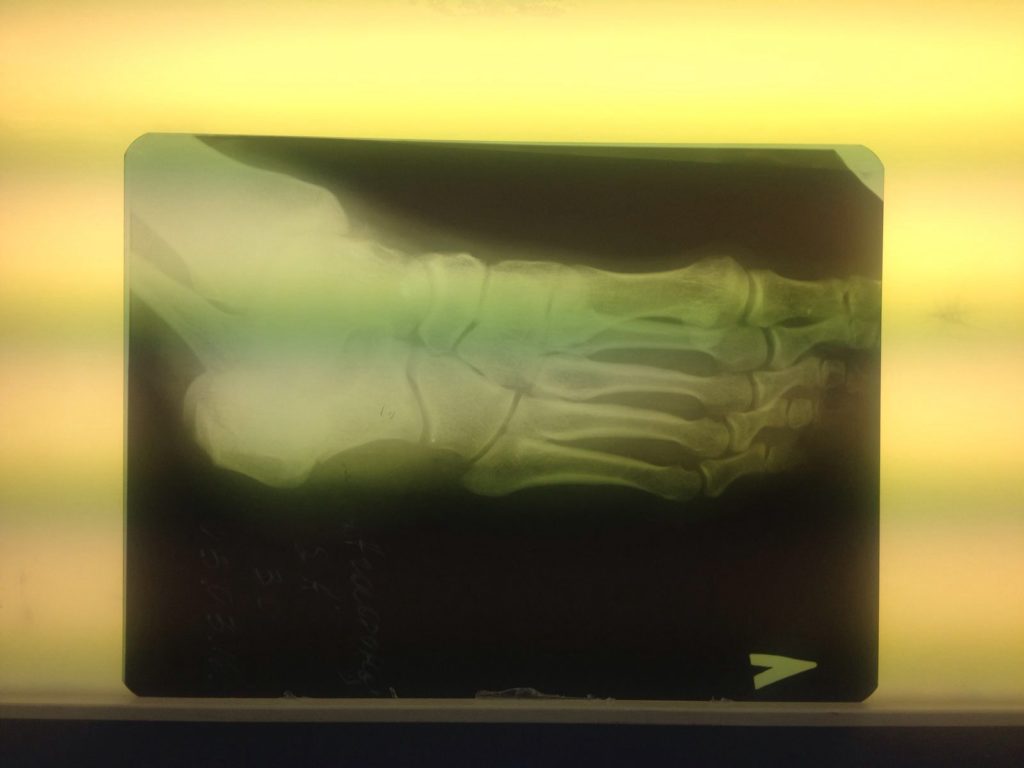

Операция – открытая репозиция, остеосинтез пяточной кости пластиной с костной ксенопластикой материалом «Остеоматрикс». На контрольных снимках в три месяца имеется консолидация перелома, миграции фиксатора нет, имеется остеоинтеграция ксенопластического материала.

Отдаленные результаты через 3 (три) месяца: